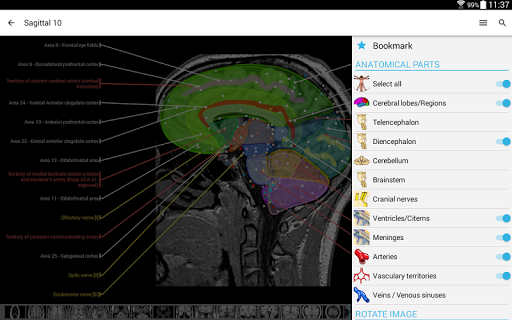

- يمكنك الآن استخدام قائمة الإعدادات والتمرير عبر الصور في نفس الوقت على الأجهزة اللوحية